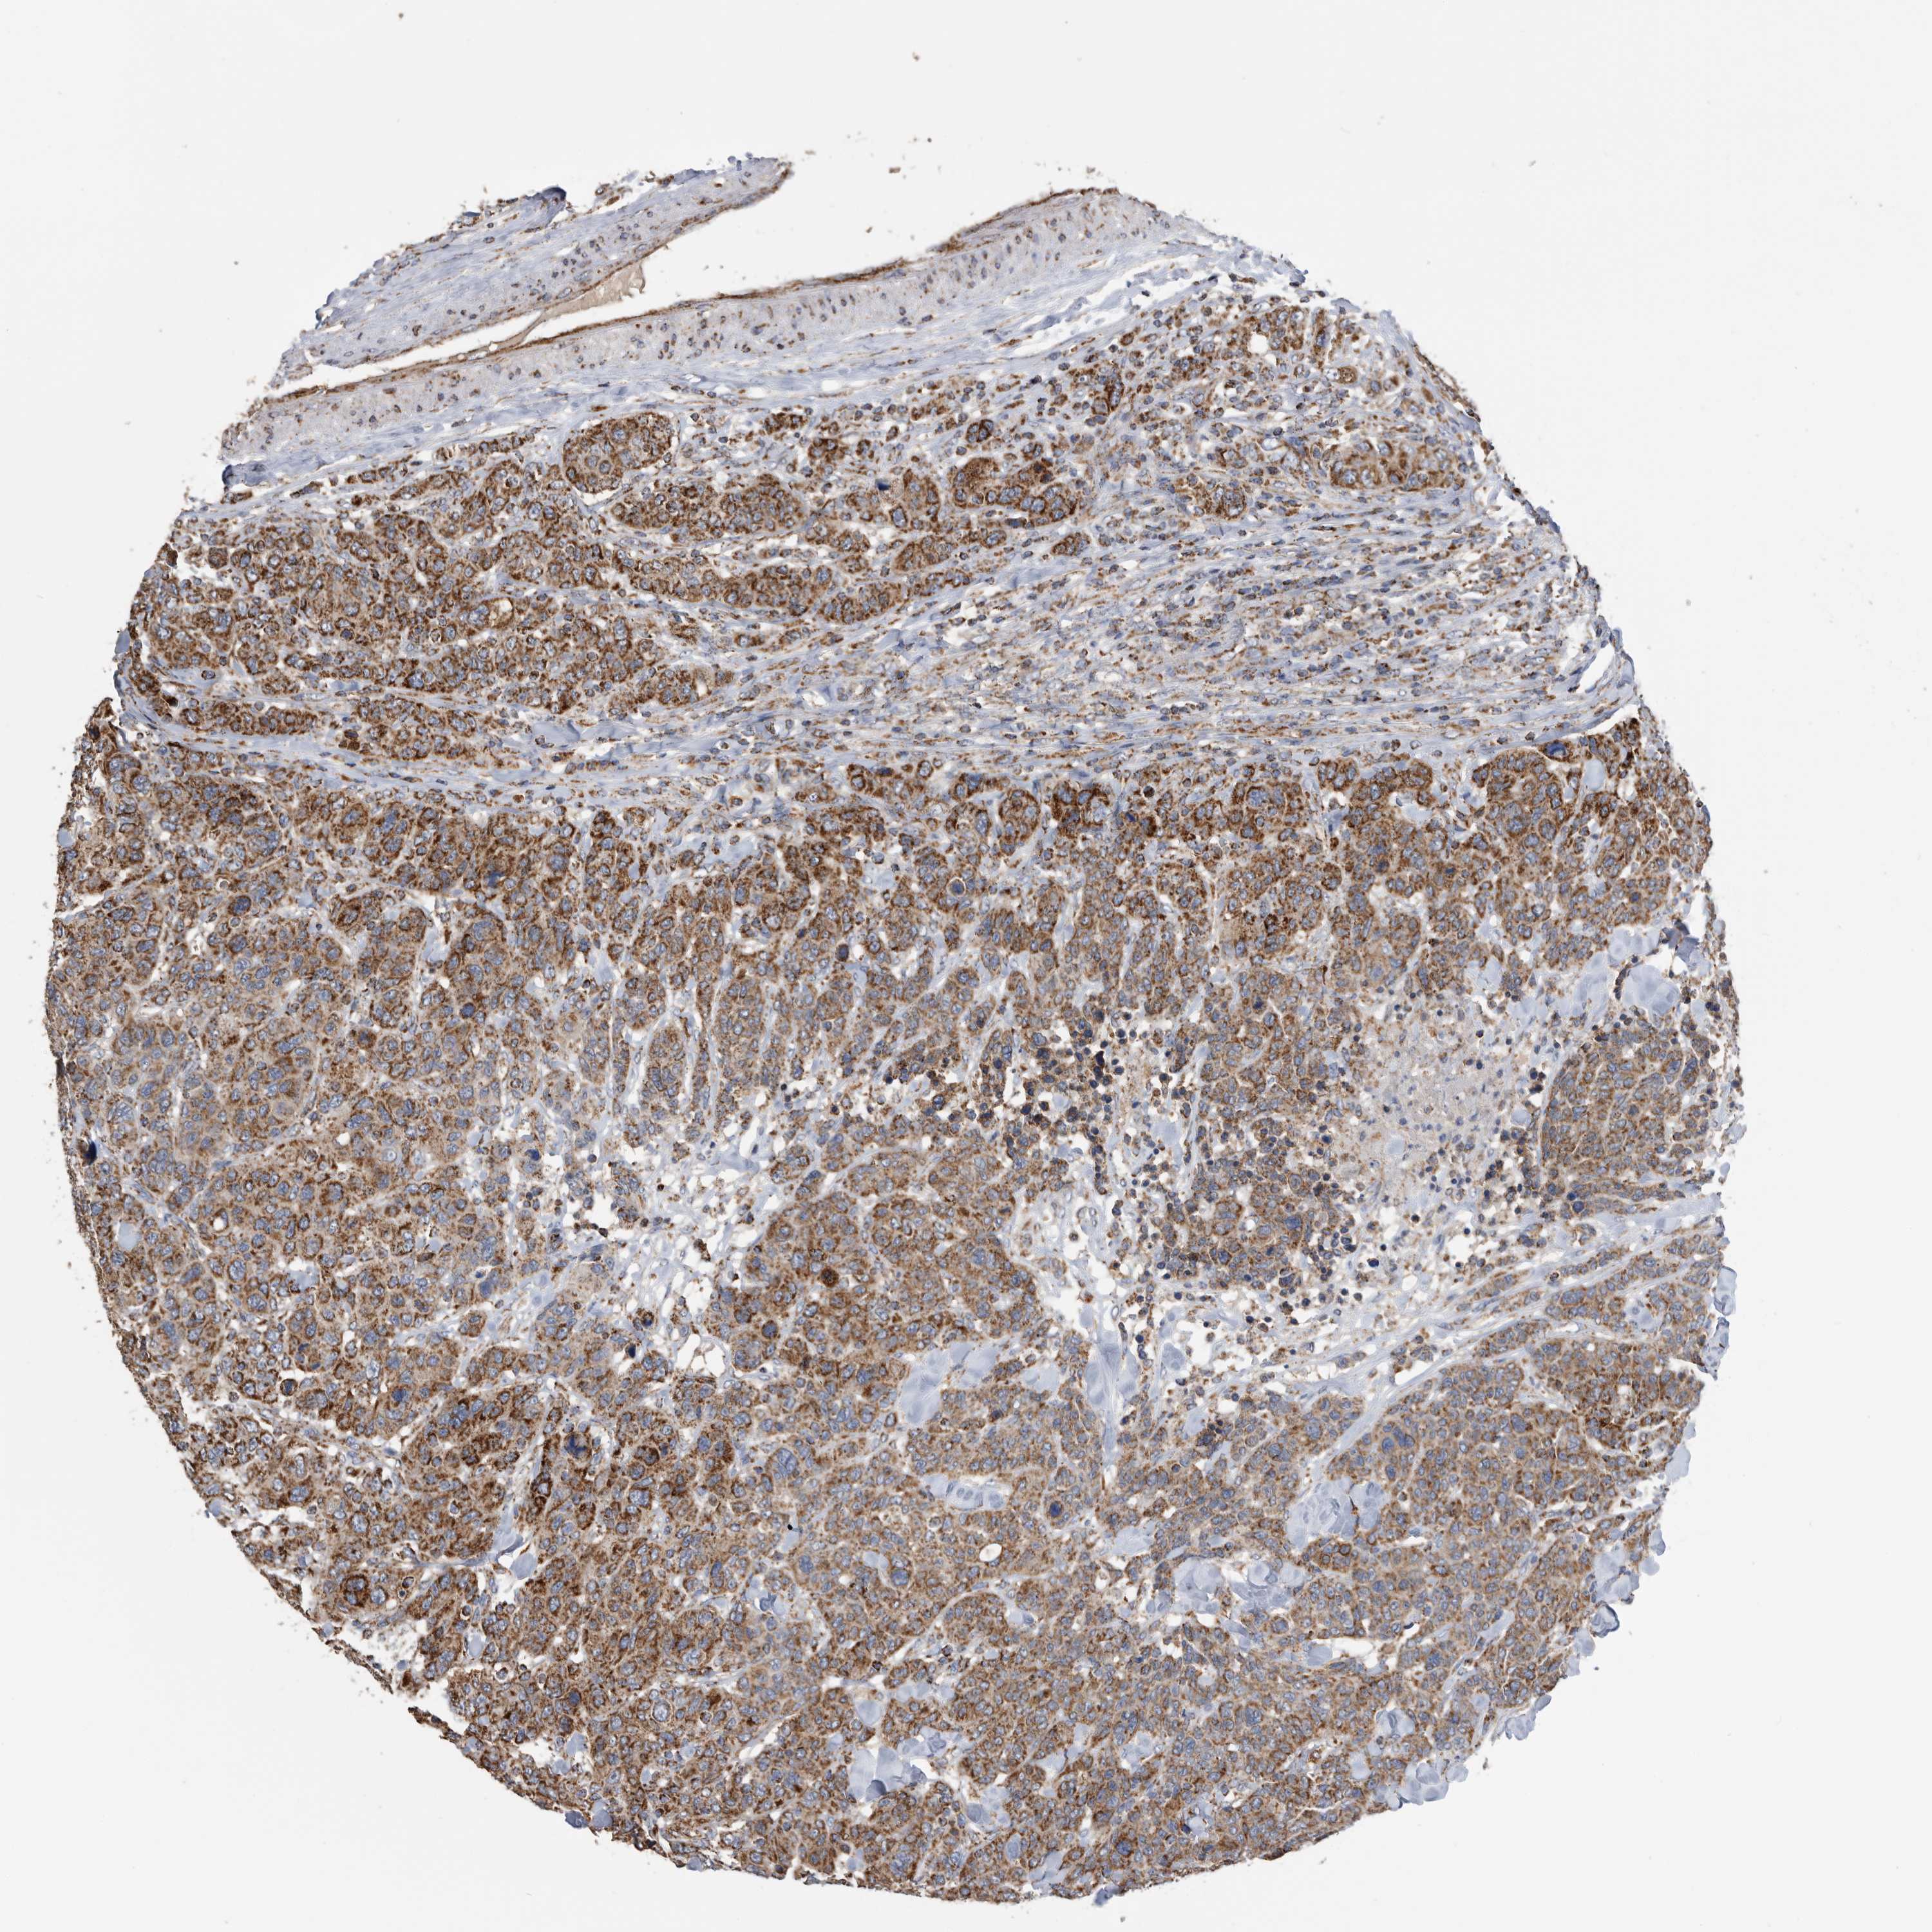

CANCER BREAST CANCER Show tissue menu

BRCA TCGA BRCA VALIDATION PROTEIN EXPRESSION